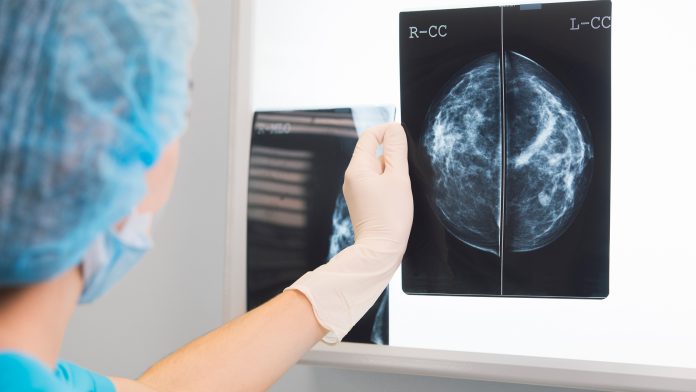

In a groundbreaking development, pioneering biotechnology company Defence Therapeutics has announced today it will be performing the final necessary studies before entering a Phase 1 trial for its innovative AccuTOX breast cancer treatment.

AccuTOX is one of Defence Therapeutics‘ premier candidates for effective breast cancer treatment and is comprised of the company’s cutting-edge AccumTM technology platform, which was initially developed to enhance the accumulation of specific proteins, antibodies (ADC’s) or antigens in target cells.

Several comprehensive studies conducted by Defence have identified a robust therapeutic function for AccumTM when administered on its own. This demonstrated that the delivery of free “naked” AccumTM (AccuTOX-001) achieved cell death of a plethora of cancer cells, including breast cancer, and was also tolerated well by other animals that experienced the same treatment regimen.

Sebastien Plouffe, the CEO of Defence Therapeutics, said: “We are actively pursuing our AccuTOX program to initiate a Phase I trial against breast cancer in Q1-Q2 of 2022. We will re-enforce our data by showing how potent is AccuTOX-001 at the killing of breast cancer in various animal models, including the use of patient-derived xenografts (PDX). The secondary objectives would be to compare the potency of AccuTOX-001 as stand-alone or combination therapy with currently used immune-checkpoint inhibitors.”

The Defence Therapeutics team is now working diligently to demonstrate that AccuTOX-001 can trigger the death of pre-establish 4T1 breast cancer in immunocompetent mice alone or in combination with anti-PD1. The team will also display the potency of the world-leading breast cancer treatment in previously characterised PDX models to ensure a good translation from mice to human studies. Once this process is completed, the team will amalgamate both the data attained and a GLP study scheduled for Q4 of 2021 to present to the FDA to achieve approval for a Phase 1 trial against breast cancer.